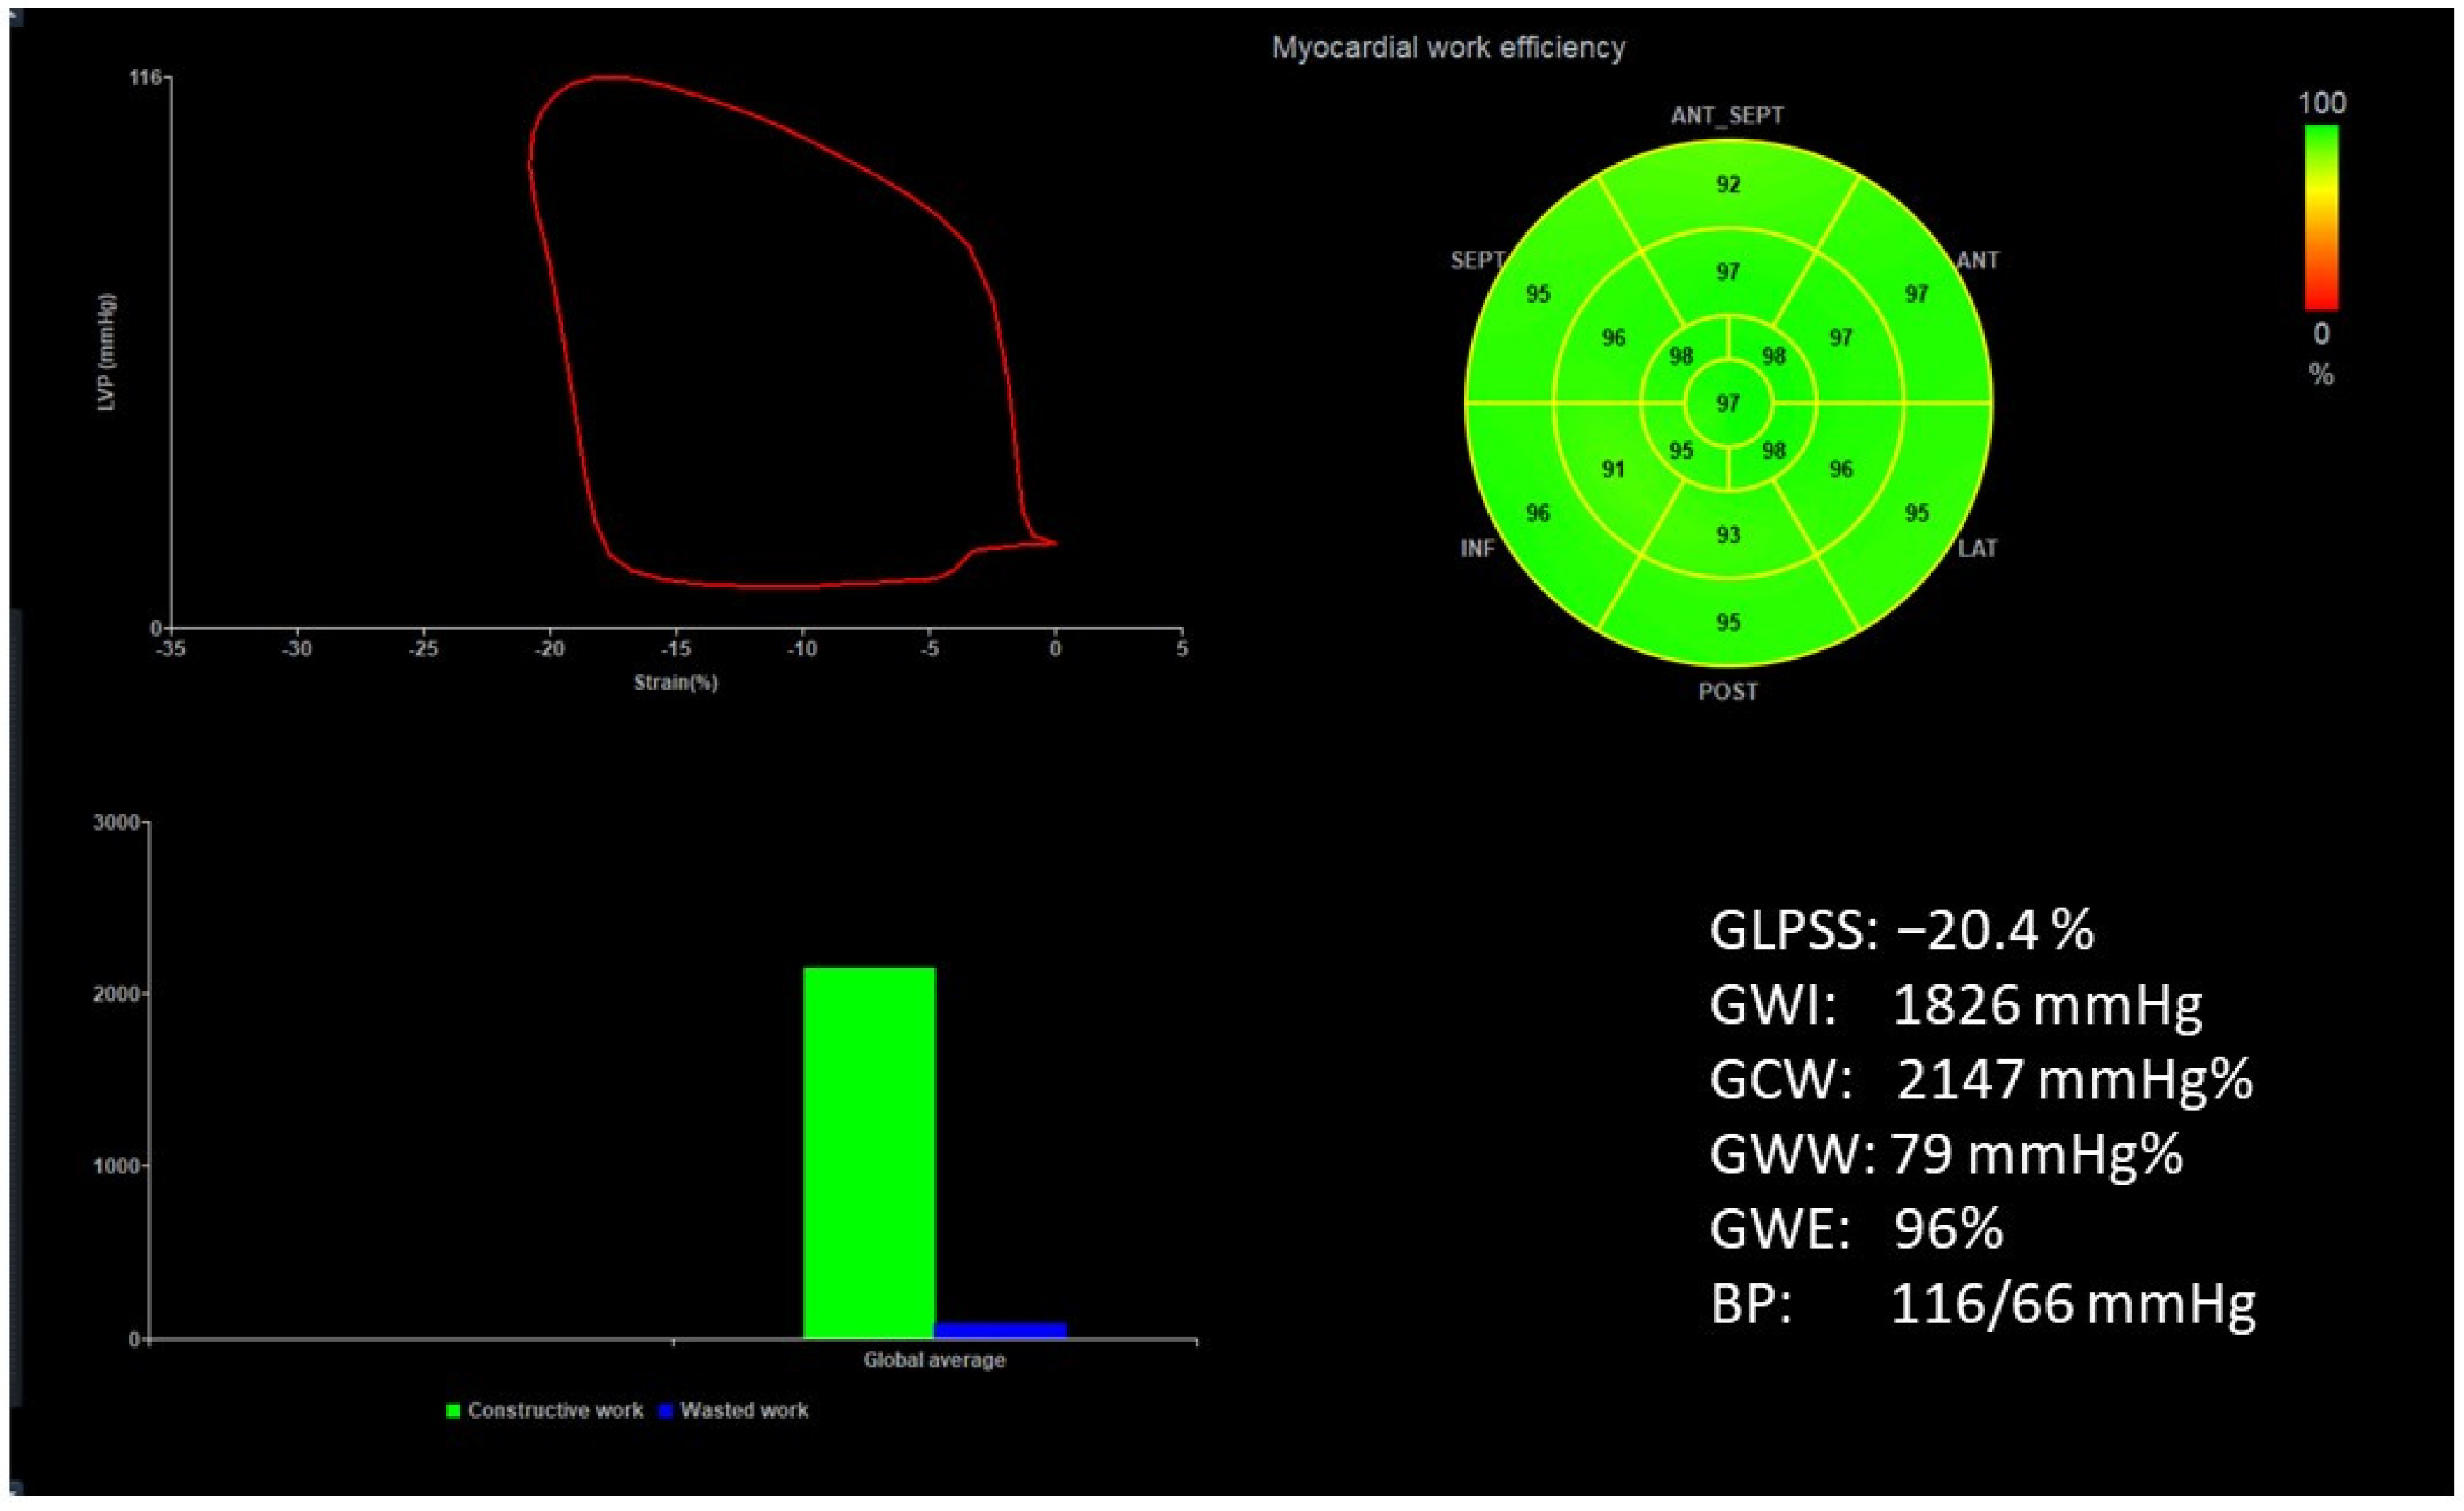

Figure 1 and Figure 2 show two contrasting examples (a healthy person and a patient after myocardial infarction and left bundle branch block) of STE curves with GLPSS, LVEF and LV pressure–strain loops and results of GWE for all LV segments.

Figure 1.

An example of echocardiography of a 30-year-old healthy male. A set of individual longitudinal strain curves for all segments shown in different colors, with the average curve shown as a white dotted line, a bull’s eye of segmental longitudinal peak systolic strains and a summary of global longitudinal peak systolic strain (GLPSS) are shown in the top panel. The LV pressure–strain loop with the bull’s eye representation of myocardial work efficiency for each of the segments and a summary of all myocardial work indices are shown in the lower panel. Abbreviations: GLPSS—global longitudinal peak systolic strain, EF—ejection fraction, GWI—global myocardial work index, GCW—global constructive work, GWW—global wasted work, GWE—global work efficiency, BP—blood pressure.